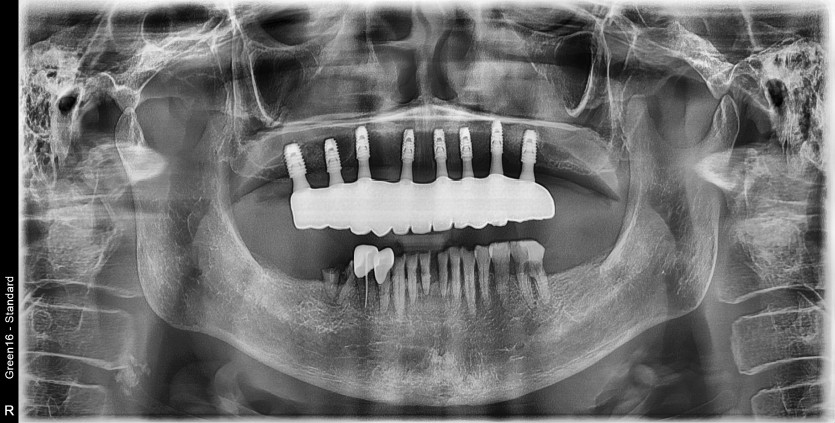

상악 풀아치 증례입니다.

8개의 임플란트로 완성하였습니다.